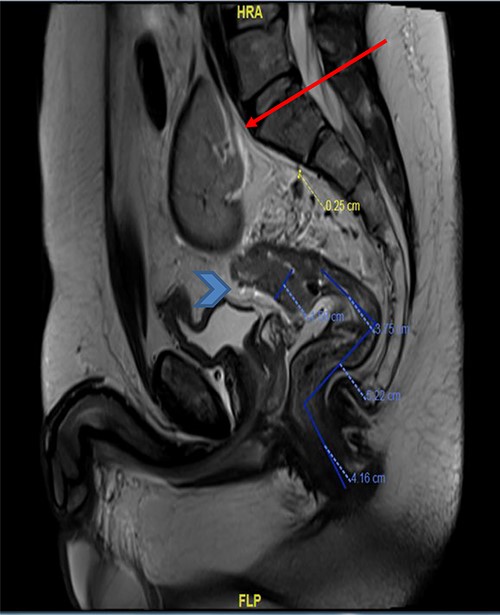

The basic lab Investigation showed Hgb level of 8.6 g/dL and CEA level of 4.8 ng/ml. On further investigation, colonoscopy revealed a large friable fungating circumferential rectal mass at 9 cm from anal verge extending to the distal sigmoid colon, it was nonobstructing with a length of 8 cm and the rest of the colon was normal. A biopsy from the mass was taken and showed invasive moderately differentiated adenocarcinoma. On further routine of radiological staging, CT of the chest, abdomen and pelvis confirmed the upper rectal mass with ectopic malrotated left kidney located in the lower abdomen and upper pelvis, opposite to L5-S1 vertebral bodies (Figs 1 and 2). There was no peritoneal disease or distant metastasis. Moreover, MRI pelvis showed again an upper rectal mass with mesorectal fat invasion and multiple lymph nodes (T3N2) and confirmed an ectopic left kidney (Figs 3 and 4).

MRI pelvis (coronal view) showed upper rectal mass with mesorectal fat involvement (arrowhead) and ectopic pelvic kidney (arrow).